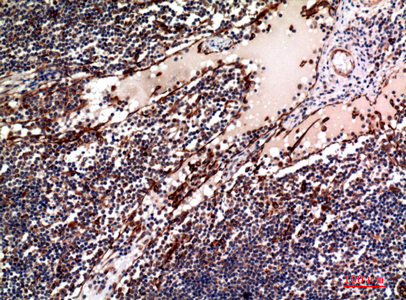

Immunohistochemistry analysis of paraffin-embedded Human lymph using OX40L antibody. High-pressure and temperature Sodium Citrate pH 6.0 was used for antigen retrieval. |